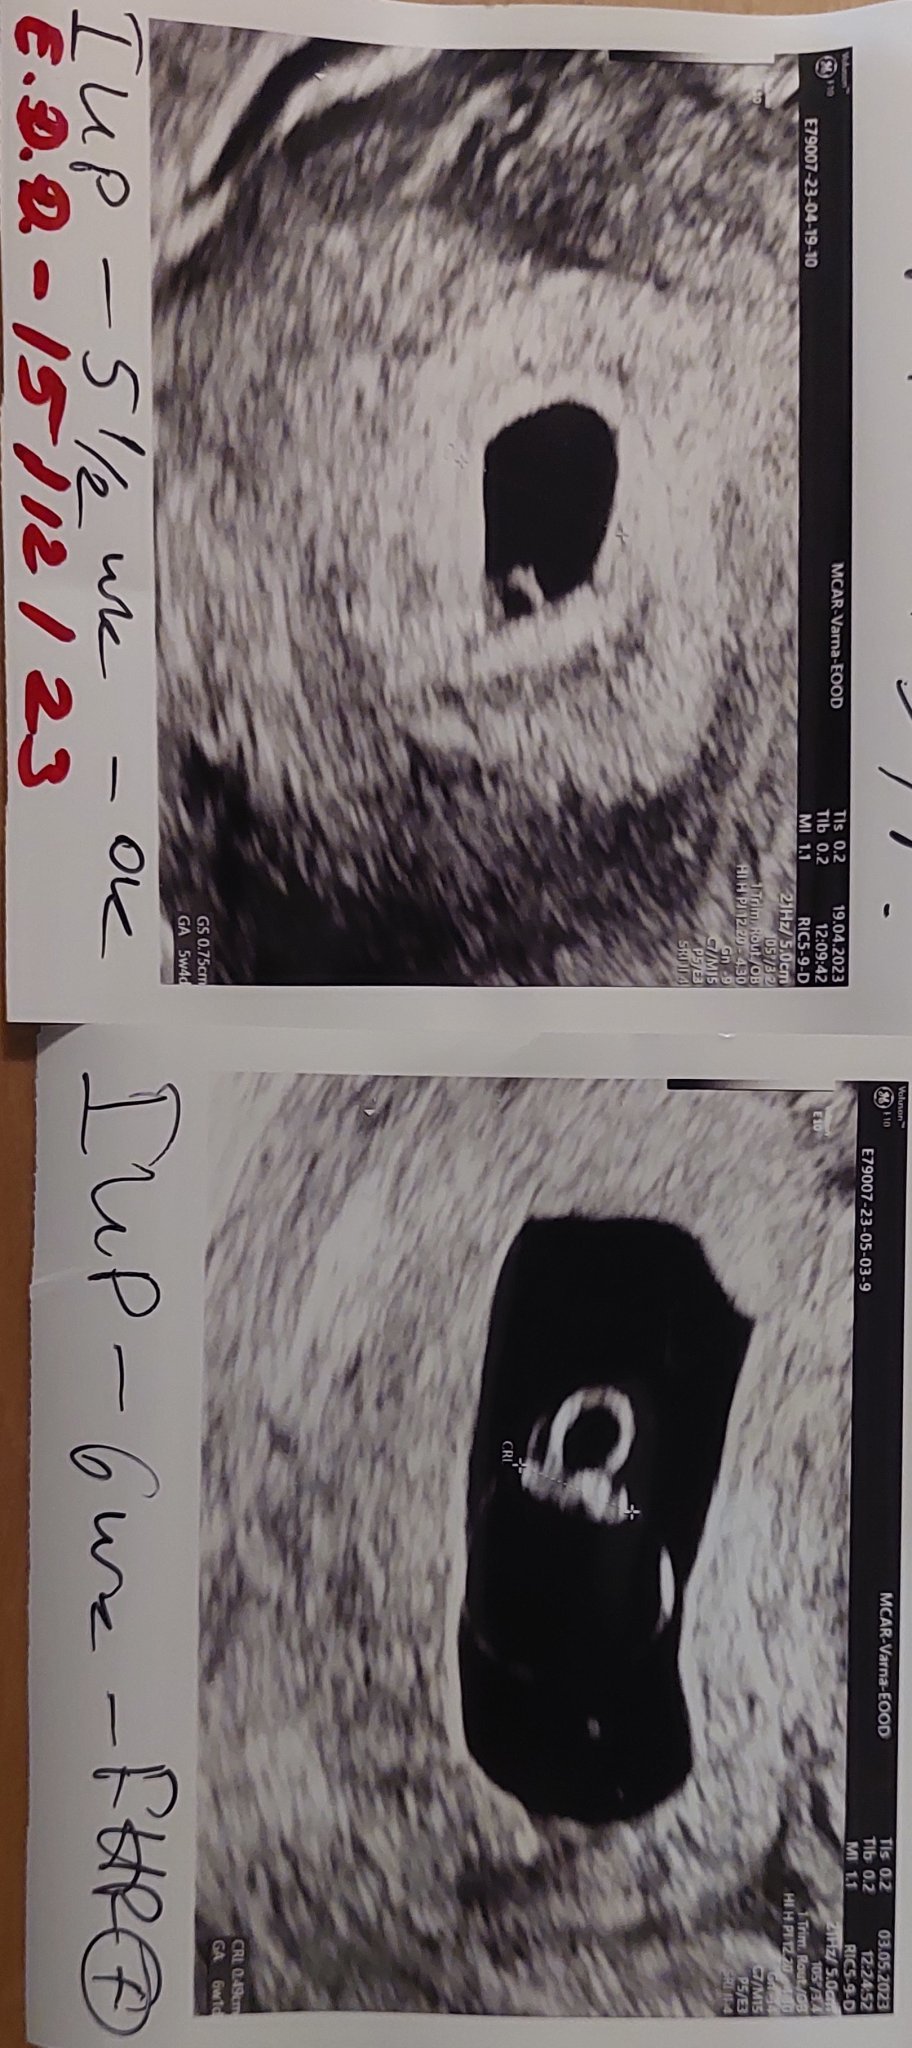

Какво представлява изображението от ехографията на 5-седмична и 2-дневна бременност?

Кога обикновено може да се види ембрионът на ултразвукова снимка?